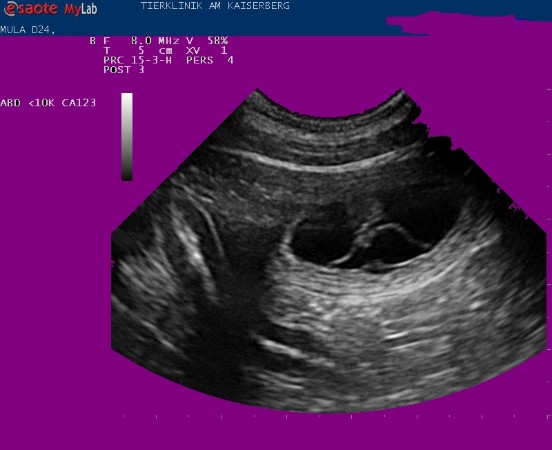

Sehr gut zu erkennen das AMNION ( die innere Eihaut)und die typische Querstreifung, die immer und auch NUR bei einer Trächtigkeit auftritt.

Heute war der Ulltraschalltermin bei Mula und es ist der 26.Tag  der Trächtigkeit festgestellt worden - die einzelnen Embryonen sind nun etwa walnussgross und sind gleichmässig im Uterus verteilt.